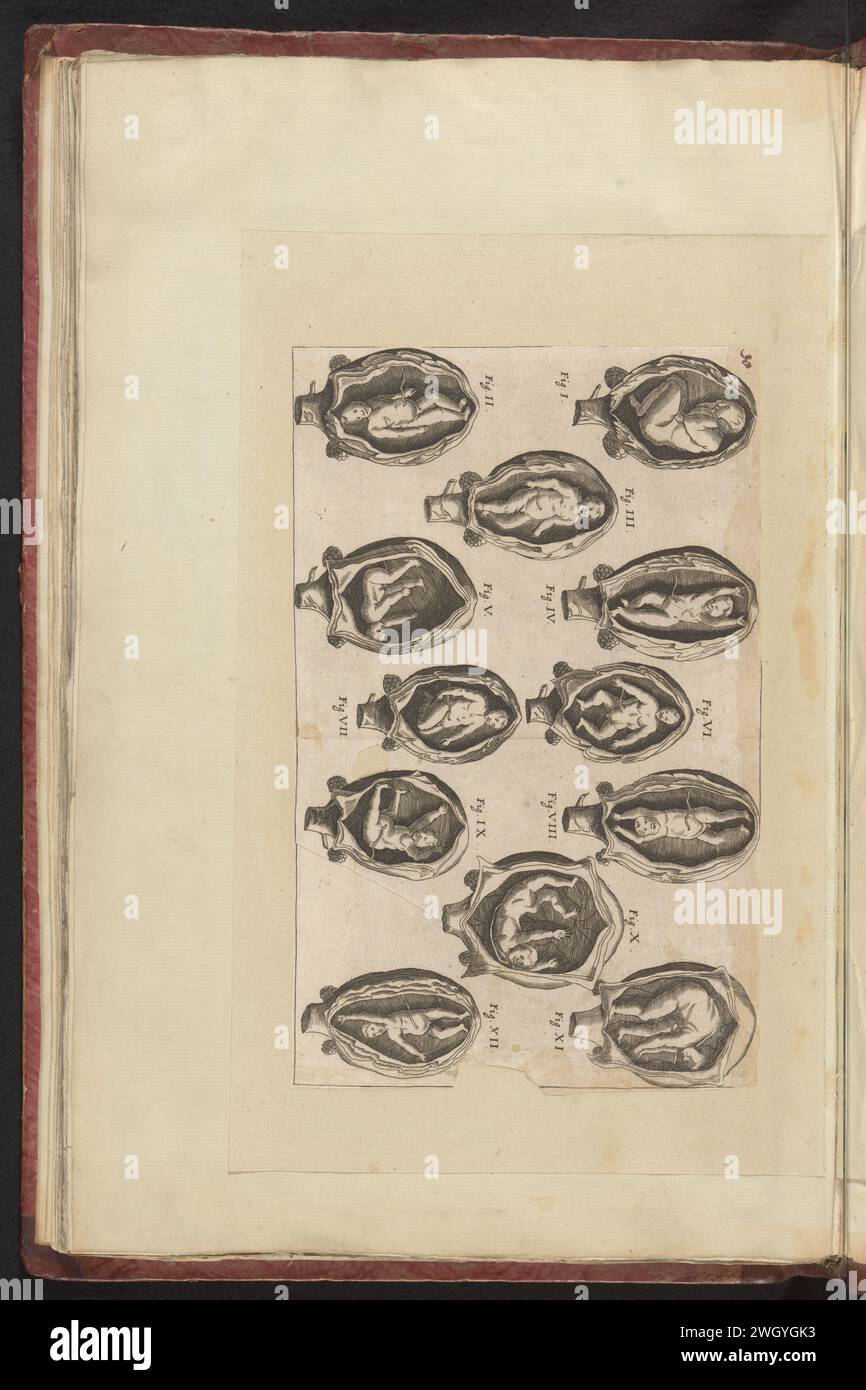

Foetal positions BR 3701 15 28r Stock Photohttps://www.alamy.com/image-license-details/?v=1https://www.alamy.com/stock-photo-foetal-positions-br-3701-15-28r-142854616.html

Foetal positions BR 3701 15 28r Stock Photohttps://www.alamy.com/image-license-details/?v=1https://www.alamy.com/stock-photo-foetal-positions-br-3701-15-28r-142854616.htmlRMJ8BGEG–Foetal positions BR 3701 15 28r

. English: Soranus of Ephesus, Gynaecology, in a Latin version of Late Antiquity: positions of the embryo in the uterus. The illustrations in this medieval manuscript are probably based on drawings by Soranus. Brussels, Bibliothèque Royale, Codex 3714, fol. 28r. Deutsch: Soranos von Ephesos, Gynäkologie, in einer spätantiken lateinischen Bearbeitung: Darstellungen von Kindslagen (Embryonen im Uterus). Die Abbildungen in dieser mittelalterlichen Handschrift gehen wohl ursprünglich auf Zeichnungen des Soranos zurück. Bruxelles, Bibliothèque Royale, Codex 3714, fol. 28r. circa 900. Soranus of Eph Stock Photohttps://www.alamy.com/image-license-details/?v=1https://www.alamy.com/english-soranus-of-ephesus-gynaecology-in-a-latin-version-of-late-antiquity-positions-of-the-embryo-in-the-uterus-the-illustrations-in-this-medieval-manuscript-are-probably-based-on-drawings-by-soranus-brussels-bibliothque-royale-codex-3714-fol-28r-deutsch-soranos-von-ephesos-gynkologie-in-einer-sptantiken-lateinischen-bearbeitung-darstellungen-von-kindslagen-embryonen-im-uterus-die-abbildungen-in-dieser-mittelalterlichen-handschrift-gehen-wohl-ursprnglich-auf-zeichnungen-des-soranos-zurck-bruxelles-bibliothque-royale-codex-3714-fol-28r-circa-900-soranus-of-eph-image188858543.html

. English: Soranus of Ephesus, Gynaecology, in a Latin version of Late Antiquity: positions of the embryo in the uterus. The illustrations in this medieval manuscript are probably based on drawings by Soranus. Brussels, Bibliothèque Royale, Codex 3714, fol. 28r. Deutsch: Soranos von Ephesos, Gynäkologie, in einer spätantiken lateinischen Bearbeitung: Darstellungen von Kindslagen (Embryonen im Uterus). Die Abbildungen in dieser mittelalterlichen Handschrift gehen wohl ursprünglich auf Zeichnungen des Soranos zurück. Bruxelles, Bibliothèque Royale, Codex 3714, fol. 28r. circa 900. Soranus of Eph Stock Photohttps://www.alamy.com/image-license-details/?v=1https://www.alamy.com/english-soranus-of-ephesus-gynaecology-in-a-latin-version-of-late-antiquity-positions-of-the-embryo-in-the-uterus-the-illustrations-in-this-medieval-manuscript-are-probably-based-on-drawings-by-soranus-brussels-bibliothque-royale-codex-3714-fol-28r-deutsch-soranos-von-ephesos-gynkologie-in-einer-sptantiken-lateinischen-bearbeitung-darstellungen-von-kindslagen-embryonen-im-uterus-die-abbildungen-in-dieser-mittelalterlichen-handschrift-gehen-wohl-ursprnglich-auf-zeichnungen-des-soranos-zurck-bruxelles-bibliothque-royale-codex-3714-fol-28r-circa-900-soranus-of-eph-image188858543.htmlRMMY76YY–. English: Soranus of Ephesus, Gynaecology, in a Latin version of Late Antiquity: positions of the embryo in the uterus. The illustrations in this medieval manuscript are probably based on drawings by Soranus. Brussels, Bibliothèque Royale, Codex 3714, fol. 28r. Deutsch: Soranos von Ephesos, Gynäkologie, in einer spätantiken lateinischen Bearbeitung: Darstellungen von Kindslagen (Embryonen im Uterus). Die Abbildungen in dieser mittelalterlichen Handschrift gehen wohl ursprünglich auf Zeichnungen des Soranos zurück. Bruxelles, Bibliothèque Royale, Codex 3714, fol. 28r. circa 900. Soranus of Eph